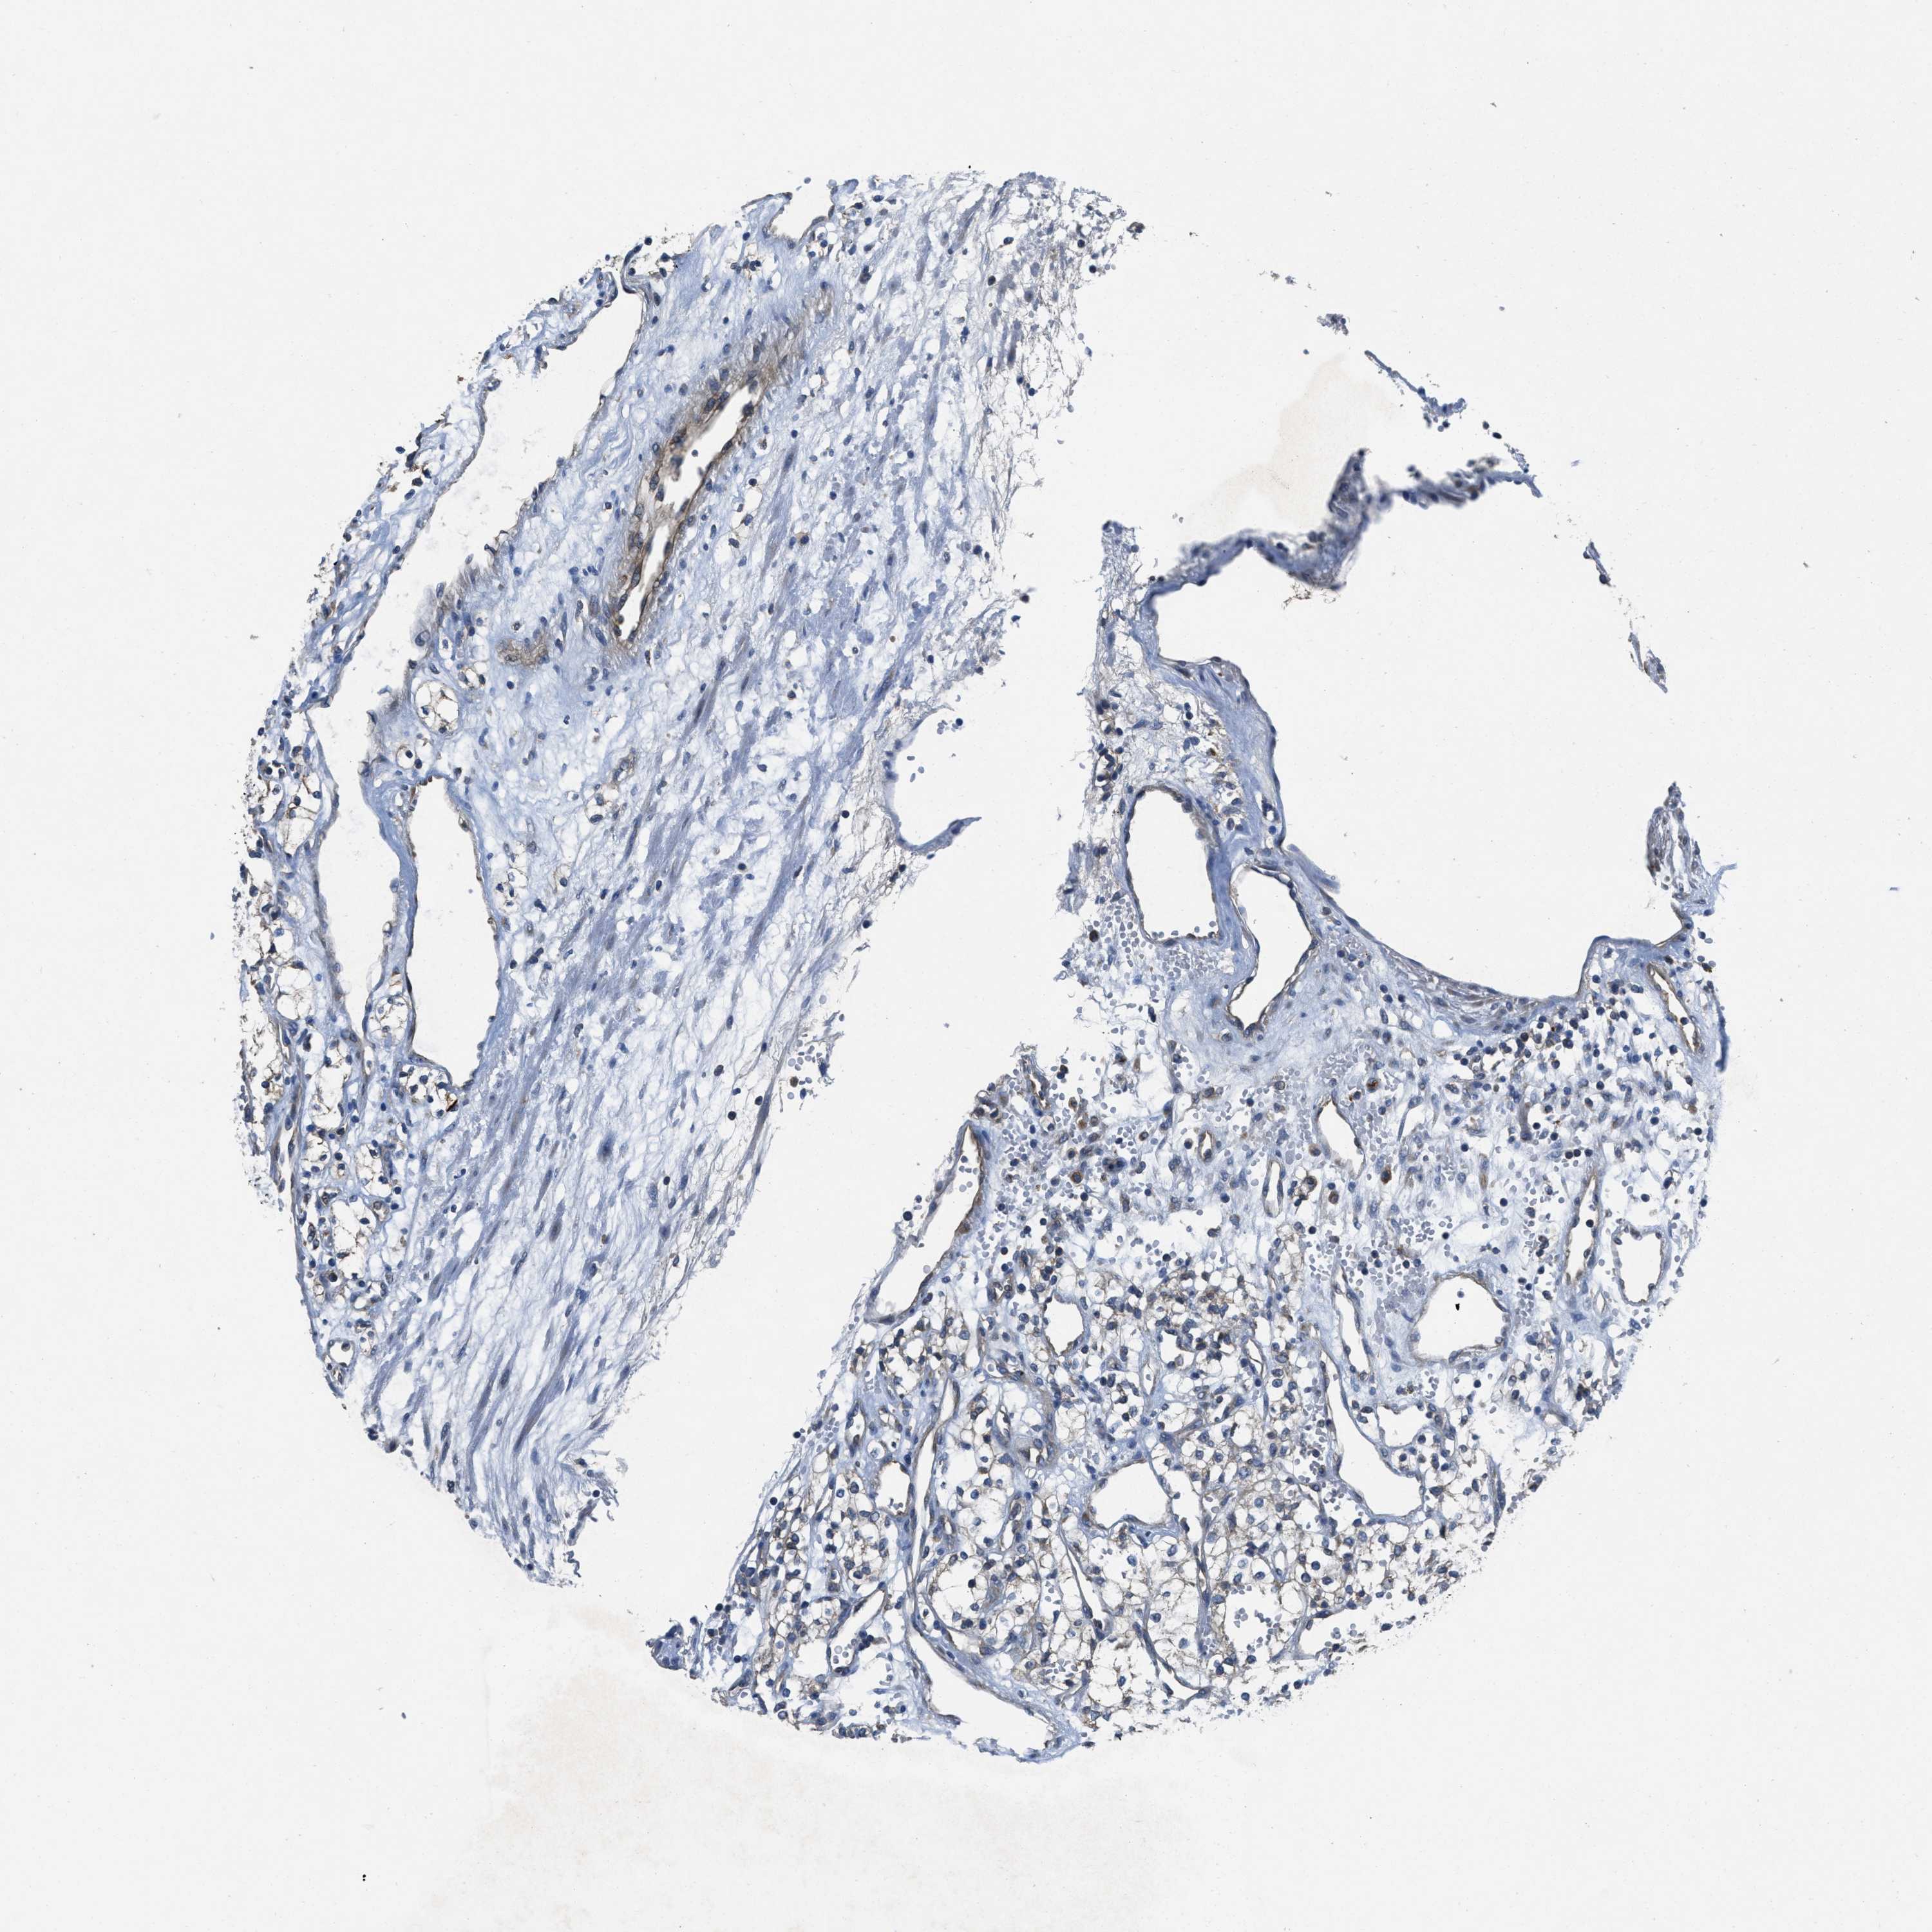

CANCER RENAL CANCER Show tissue menu

KICH TCGA KIRC TCGA KIRC VALIDATION KIRP TCGA PROTEIN RCC CPTAC PROTEIN EXPRESSION